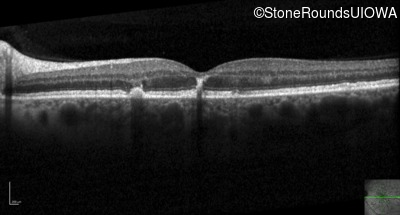

Optical Coherence Tomography - Left - 20/40 +1 sc

Exemplar / OCT Stack

OCT Stack